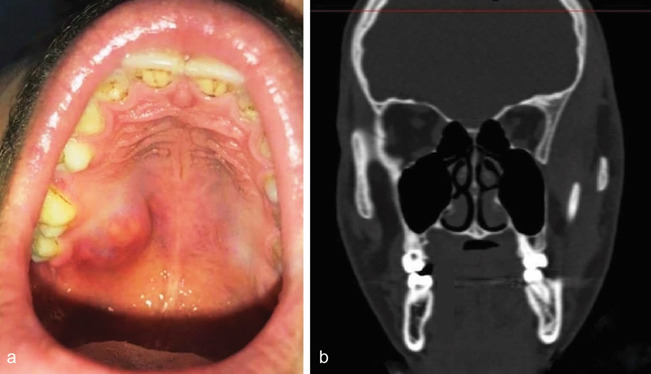

梭形细胞血管瘤(SCH),以前称为“梭形细胞血管内皮瘤”,是一种罕见的良性血管瘤的组织学变异,其特征是存在两个对比区,第一个区表现为巨大的扩张的海绵状空间,裂缝状血管空间可显示清晰的内皮空泡,类似脂肪细胞。SCH常被认为是假肉瘤;由于它与卡波西肉瘤相似,对口腔病理学家的诊断提出了挑战。迄今为止,头颈部共报告了13例SCH,而口腔内仅报告了6例。我们报告一例罕见的位于硬腭的SCH,其组织病理检查与卡波西氏肉瘤相似。EGR、cd31、HHV - 8等标志物的表达是SCH的最终诊断依据。据我们所知,EGR和HHV - 8标志物从未用于口腔内SCH;因此,本报告强调使用免疫组织化学诊断SCH。

Spindle cell hemangioma (SCH), formerly called "spindle cell hemangioendothelioma", is a rare benign histological variant of hemangioma characterized by the presence of two contrast zones, the first zone exhibits large dilated cavernous space with slit-like vascular spaces may show clear endothelial vacuoles resembling fat cells. SCH is often considered as pseudosarcomatous entity; it imposes a diagnostic challenge for oral pathologists due to its resemblance with Kaposi sarcoma. A total of 13 cases of SCH have been reported in the head and neck region to date and only 6 cases have been reported inside the oral cavity. We present a rare case of SCH located on the hard palate, which imitated Kaposi's sarcoma on histopathological examination. The expressions of various markers including EGR, CD 31, and HHV 8 yielded the final diagnosis of SCH. The markers EGR and HHV 8 have never been used in intraoral SCH before to the best of our knowledge; hence, the present report highlights the use of immunohistochemistry for the diagnosis of SCH.